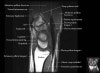

손목 관절의 MRI 단면 영상

- Axial section

Axial T1 evaluates the tendons of the wrist and carpal tunnel, including the flexor retinaculum.

Axial PD fat suppressed evaluates the tendons of the wrist and carpal tunnel, including the median nerve.